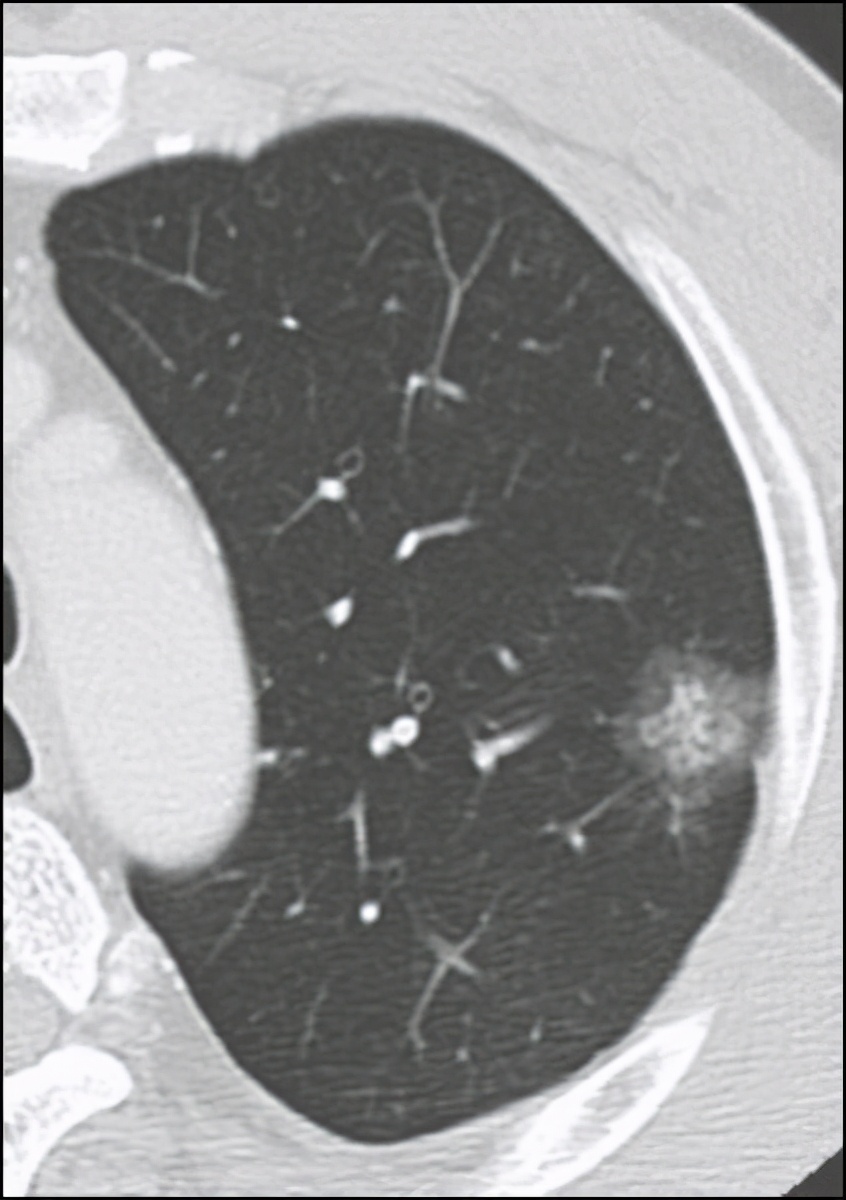

最近网络平台一个患者咨询 , 这个患者50岁 , 体检发现肺部2cm的混合磨玻璃结节 , 抗炎治疗后复查无变化 , 考虑恶性结节 , 当地医院建议病人手术 , 但这个患者对手术有点顾虑 , 又听说可以做微波介入治疗 , 过来咨询到底是微创手术好 , 还是微波介入好?

微波消融有点像微波炉的原理 , 使东西内部加热升温 。 微波消融是在CT引导下将一根微波针穿刺至肿瘤中心区域 , 由它释放的微波磁场可以使周围的分子高速旋转运动并摩擦升温 , 当温度升高到60℃以上时 , 肿瘤细胞的蛋白质变性 , 细胞凝固、坏死 , 从而达到“烧死”肿瘤的目的 , 坏死的细胞逐渐被体内巨噬细胞所清除 , 其周围的正常组织受较少损伤或不受损伤 。

微波消融主要适用于原位肺腺癌或微浸润肺腺癌患者、肺结节胸腔镜术后发现新的高危肺结节 , 双肺多发高危结节 , 全身情况无法耐受手术的早期肺癌患者、肺癌瘤体生长位置较差无法手术的患者 。 一般来说 , 3厘米以下的肺结节可以同时进行穿刺活检和微波消融 。